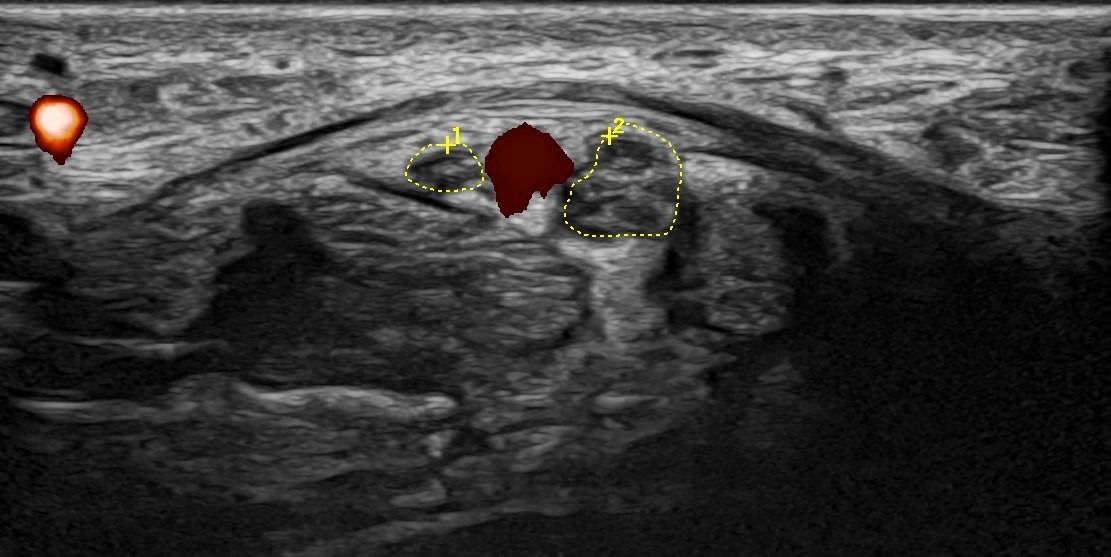

- Entrapment Syndromes (carpal tunnel syndrome, cubital tunnel syndrome, tarsal tunnel syndrome, meralgia paresthetica)

- Focal Lesions (tumors, neuromas)